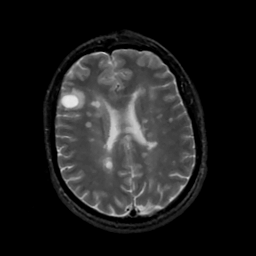

MR Study #5, March 10, 1991 -- Slice #33